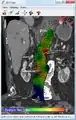

Abdominal aortic endoprosthesis, CT scan, original aneurysm marked in blue